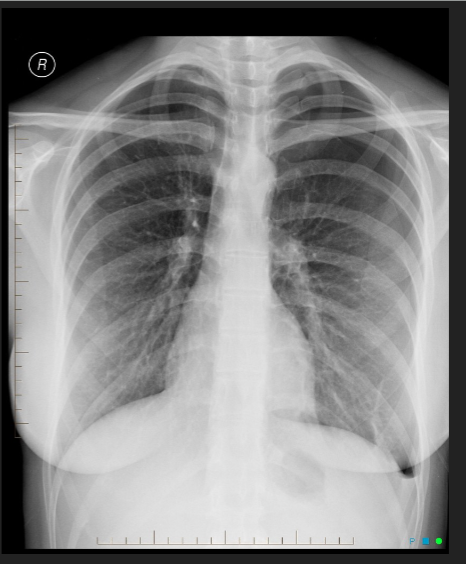

26

pleural effusion